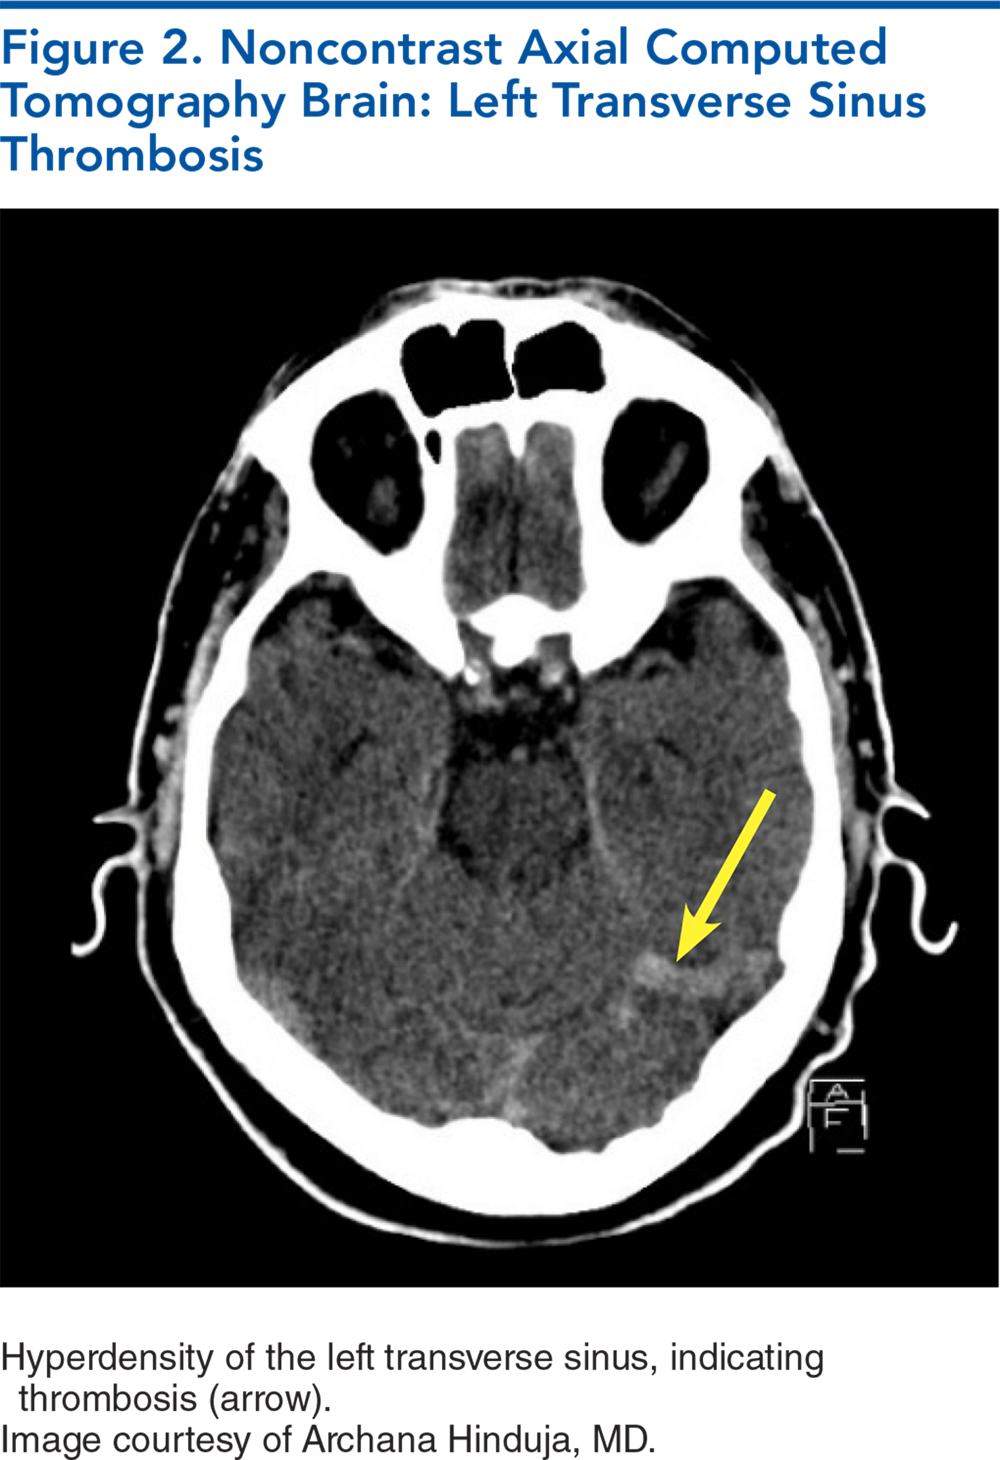

Cerebral venous sinus thrombosis is a rare cause of stroke with an overall good prognosis. It predominantly affects women of reproductive age and patients with prothrombotic conditions. It has a diverse presentation that includes headache, seizures, focal neurological deficits, and encephalopathy. A strong index of suspicion is required to make a prompt diagnosis and initiate early management. Despite aggressive care, death or functional dependence occurs in 10% to 15% of patients. This review provides an overview of the literature and recent guidelines on the emergency department approach and the therapeutic challenges in the management of patients with cerebral venous sinus thrombosis.